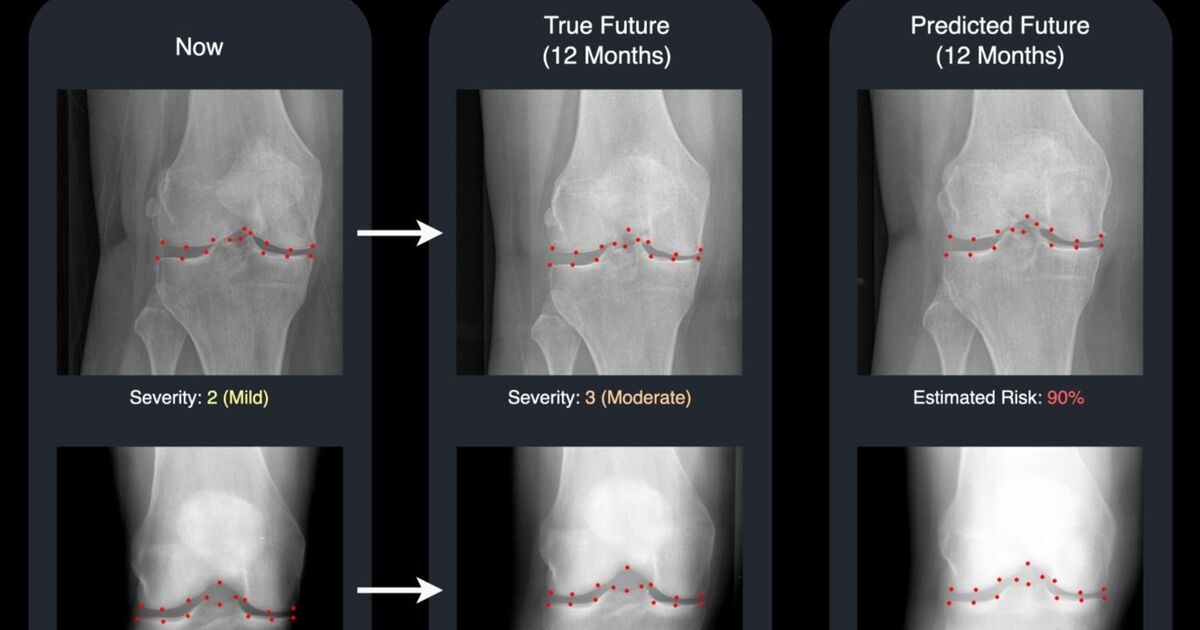

Now, a new study by the University of Surrey shows their own developed technology uses advanced machine learning to generate a realistic "future" X-ray alongside a risk score for disease progression in the knee. These two outputs combined can give doctors and patients a clear, visual forecast of how the condition may develop over time.

"Our system not only predicts the likelihood of your knee getting worse - it actually shows you a realistic image of what that future knee could look like.

"Seeing the two X-rays side by side - one from today and one for next year - is a powerful motivator.

Using an advanced generative model, called a diffusion model, the Surrey system generates a "future" version of a patient’s knee X-ray and highlights 16 key points in the joint.

These points add transparency by showing which areas the AI is monitoring for changes, making the system easier for clinicians to understand and trust.